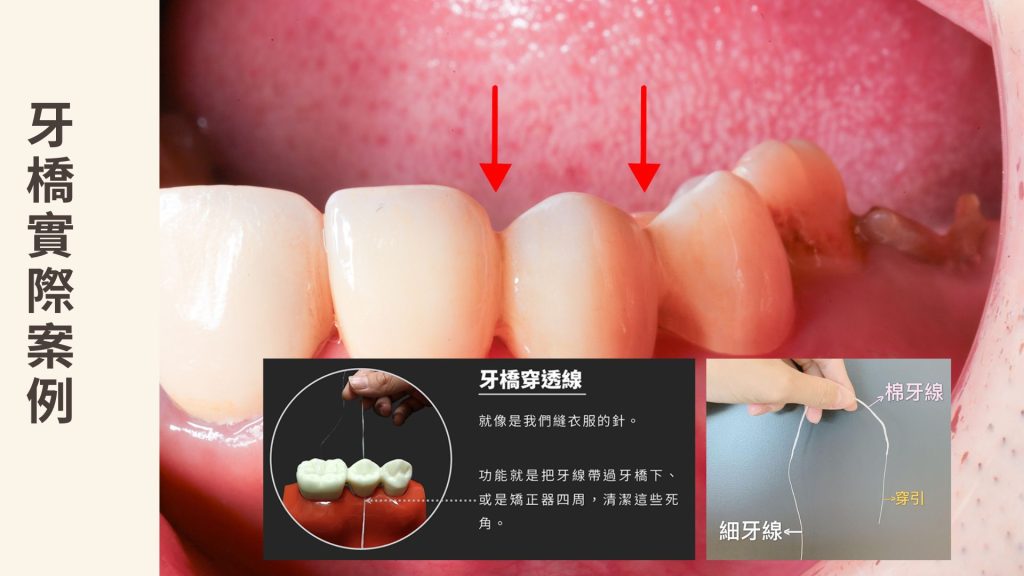

牙橋做好之後,不只是裝上去而已,後續也要清得乾淨。

因為橋體下方不像一般牙縫能直接用牙線通過,通常需要搭配牙線穿引器或超級牙線(super-floss),把牙線帶入底部,才能把容易堆積的牙菌斑與食物殘渣清掉。

清潔不佳所帶來的下一個議題,便是開始蛀牙、牙橋晃動後拆除再治療問題

Q4|做牙橋之後要怎麼清?

A:橋體下方通常需要搭配牙線穿引器或超級牙線(super floss)清潔,不能只靠一般刷牙。